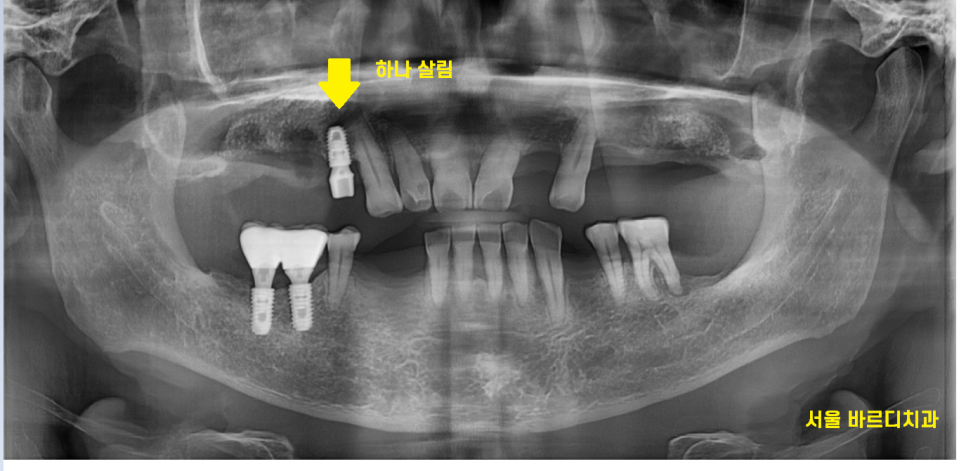

23.12.16

병원을 처음 방문하셨을때부터

이미 심어둔 임플란트가 있었습니다.

치아가 빠진 부분도 많고

치석도 많은 상태입니다.